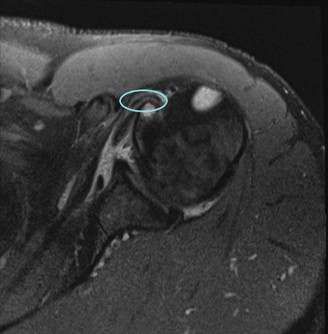

A 45-year-old carpenter presents with shoulder pain that has been ongoing for the last 3 months. He denies any significant injury. He describes night pain and significant discomfort at work. His imaging is shown in Figure 2–9. What is the most likely diagnosis?

Figure 2–9_From Shi LL, Mullen MG, Freehill MT, et al. Accuracy of Long Head of the Biceps Subluxation as a Predictor for Subscapularis Tears. _Arthroscopy 2015;32(4):615–619.

The correct answer is (A). Medial subluxation of the biceps tendon as seen in this MRI is commonly associated with a tear of the subscapularis tendon which attaches to the lesser tuberosity. This patient’s pain may in part be attributable to the subscapular tear and this should be evaluated for during physical examination. Supraspinatus tears (Answer B) cannot be easily visualized on axial views and are not associated with medial biceps subluxations. A labral tear and ALPSA lesion (Answers C and D) are not seen on the images provided. The question stem and MRI are not suggestive of shoulder instability (Answer E). Objectives: Did you learn...? Diagnose and treat acute rotator cuff tears?